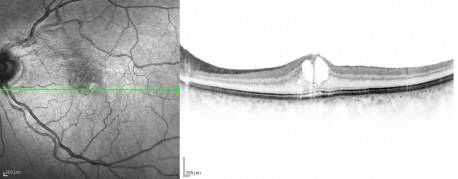

Bei der feuchten altersbedingten Makuladegeneration (AMD) kommt es zu Strukturveränderungen der Netzhaut im Bereich der Stelle des staärksten Sehens (Macula), die sehr genau mit der OCT dargestellt werden können.

Man sieht, in welcher Schicht und in welchem Ausmaß Schädigungen vorliegen. Dies ist in bestimmten Stadien der feuchten AMD hilfreich als ergänzende Information zu den anderen erhobenen Befunden und zur Beurteilung des Krankheitsverlaufs unter Therapie durch intravitreale Injektionen (IVOM).